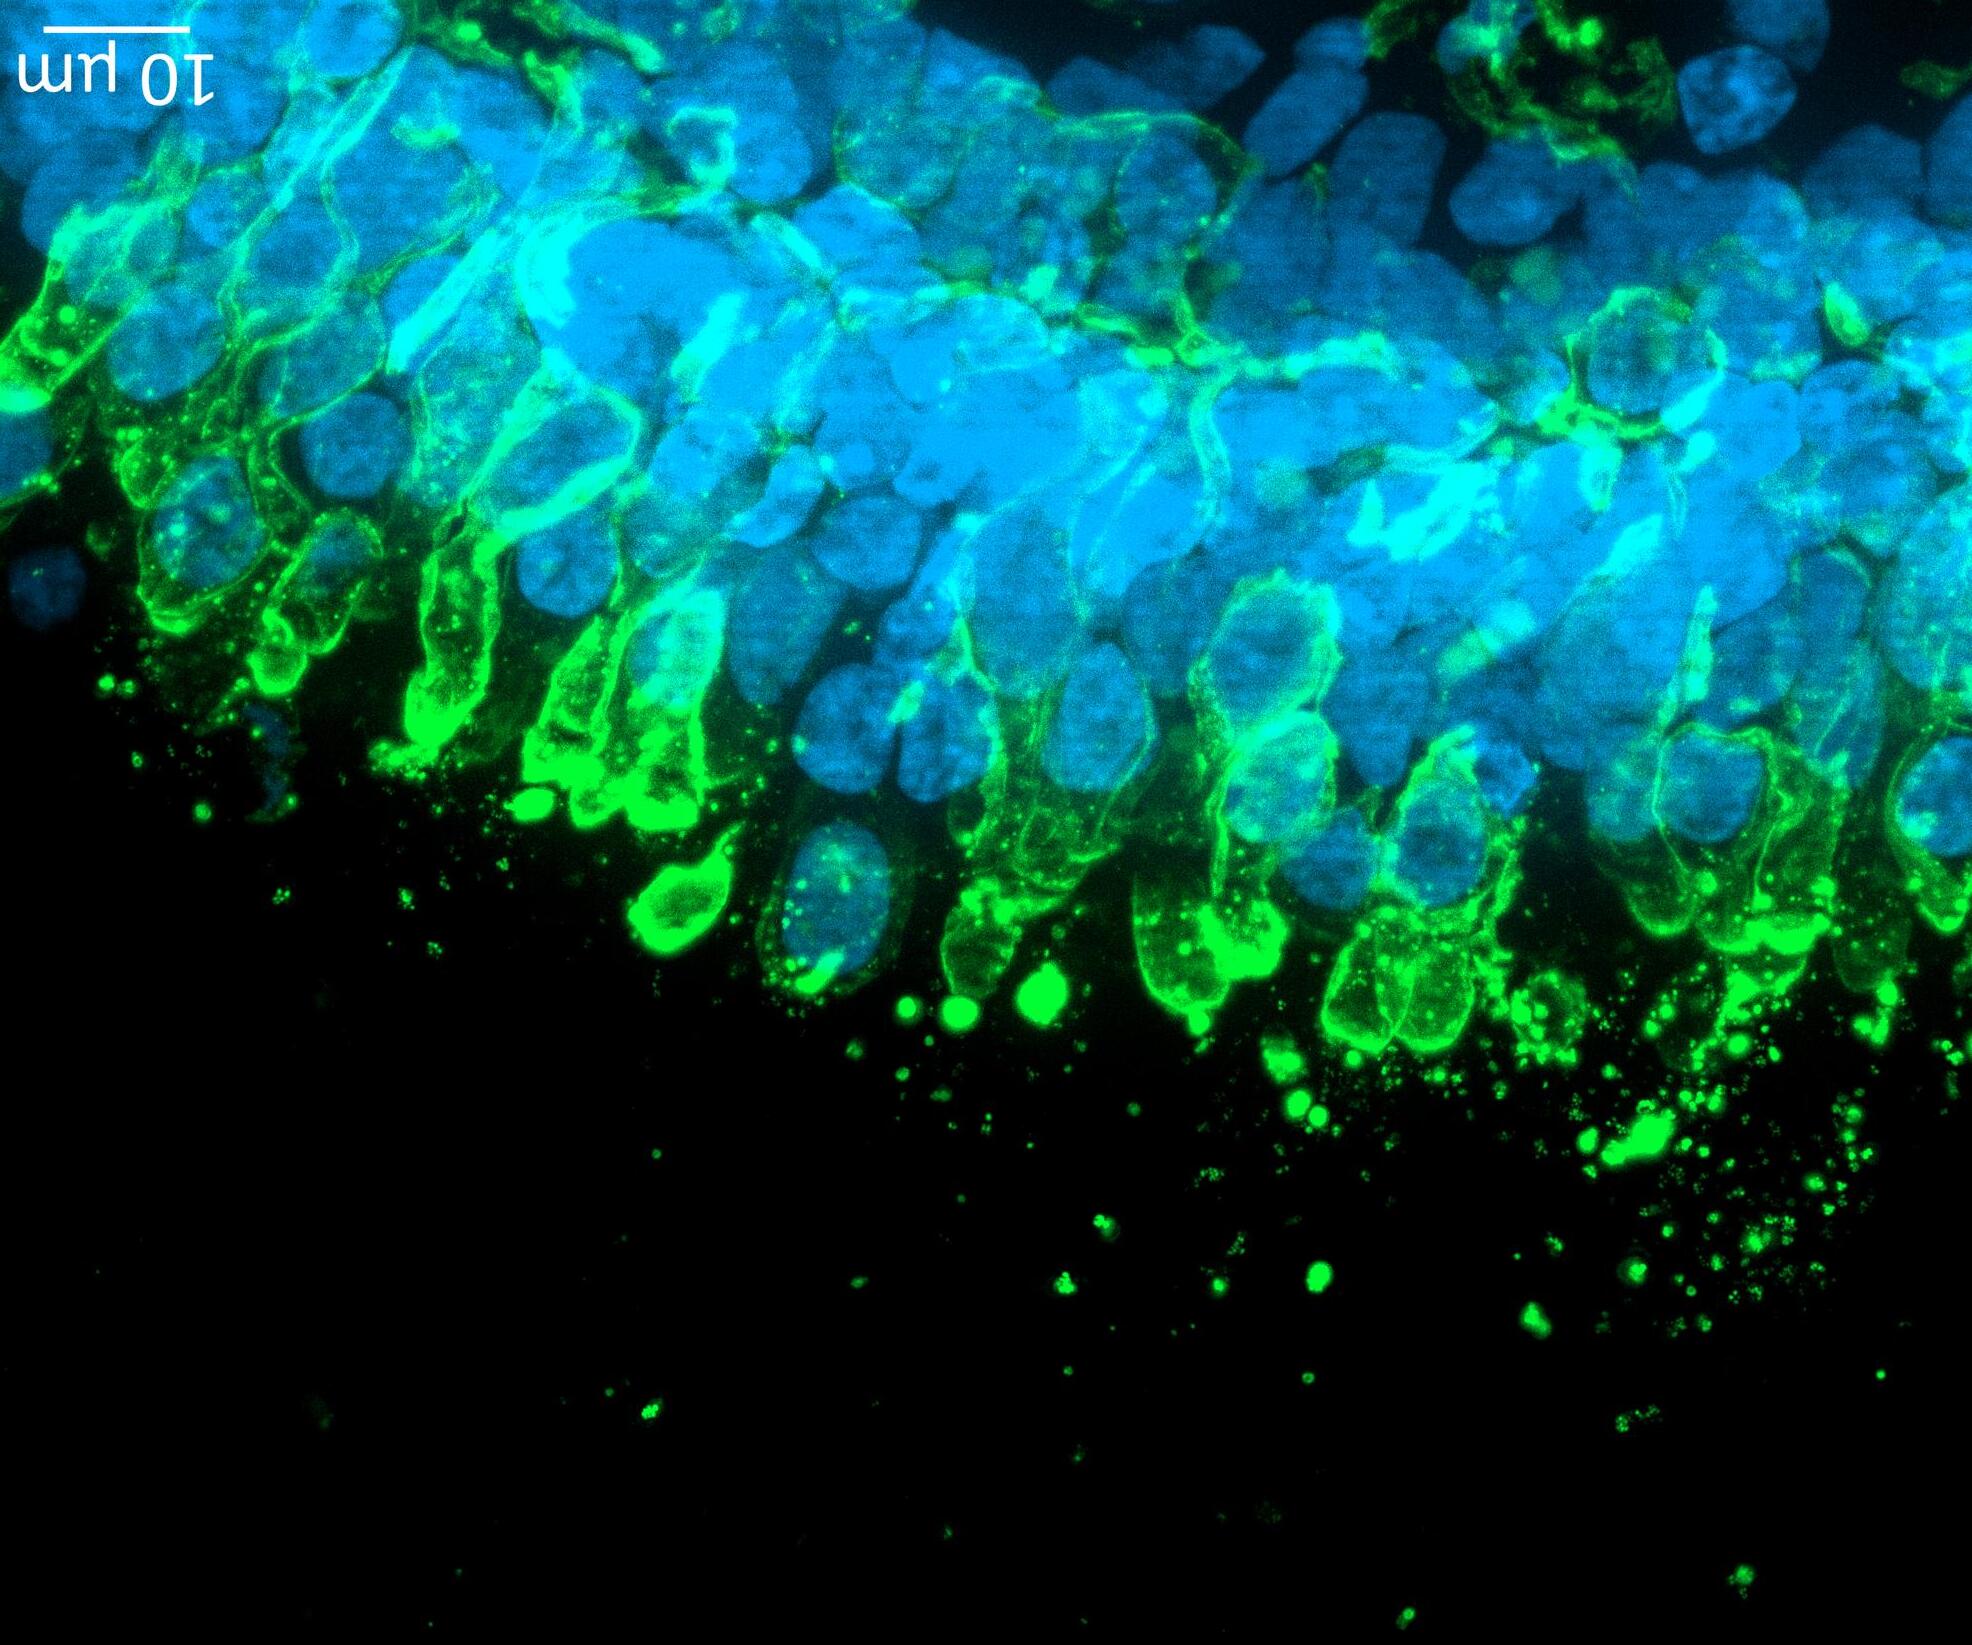

74 Use of the aProximateTM Proximal Tubule Cell Model for the Evaluation of Safety and Renal Accumulation of Radioconjugates and Large Molecules

The aProximateTM Proximal Tubule Cell (PTC) model offers a cutting-edge platform for the evaluation of drug-induced nephrotoxicity, radioconjugate retention and the accumulation of large molecules in the proximal tubule. Colin Brown of NewCells outlines the advantages of using the aProximateTM PTC model in predicting and assessing renal safety in the early stages of drug development.

proximal tubule cell model for early assessment of renal safety in biologics.